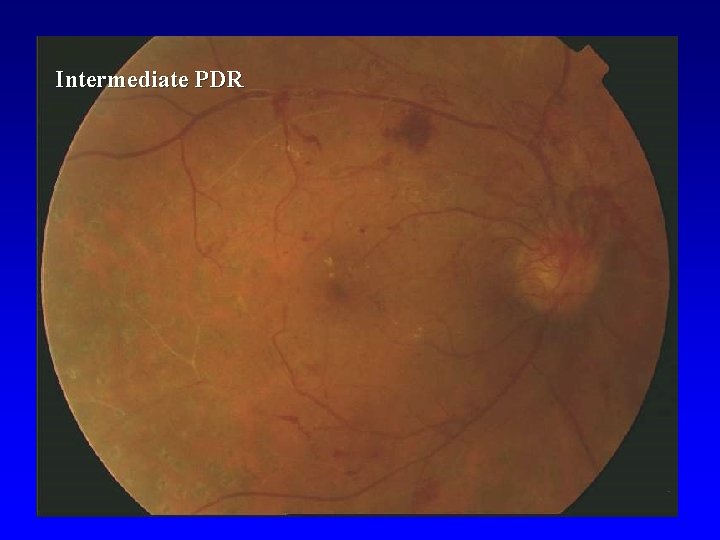

Proliferative DR (PDR) • • • Light Intermediate Fully advanced VH- vitreous hemorrhage, PRHpreretinal hemorhage, TRD- retinal detachment at center of macula

Intermediate PDR